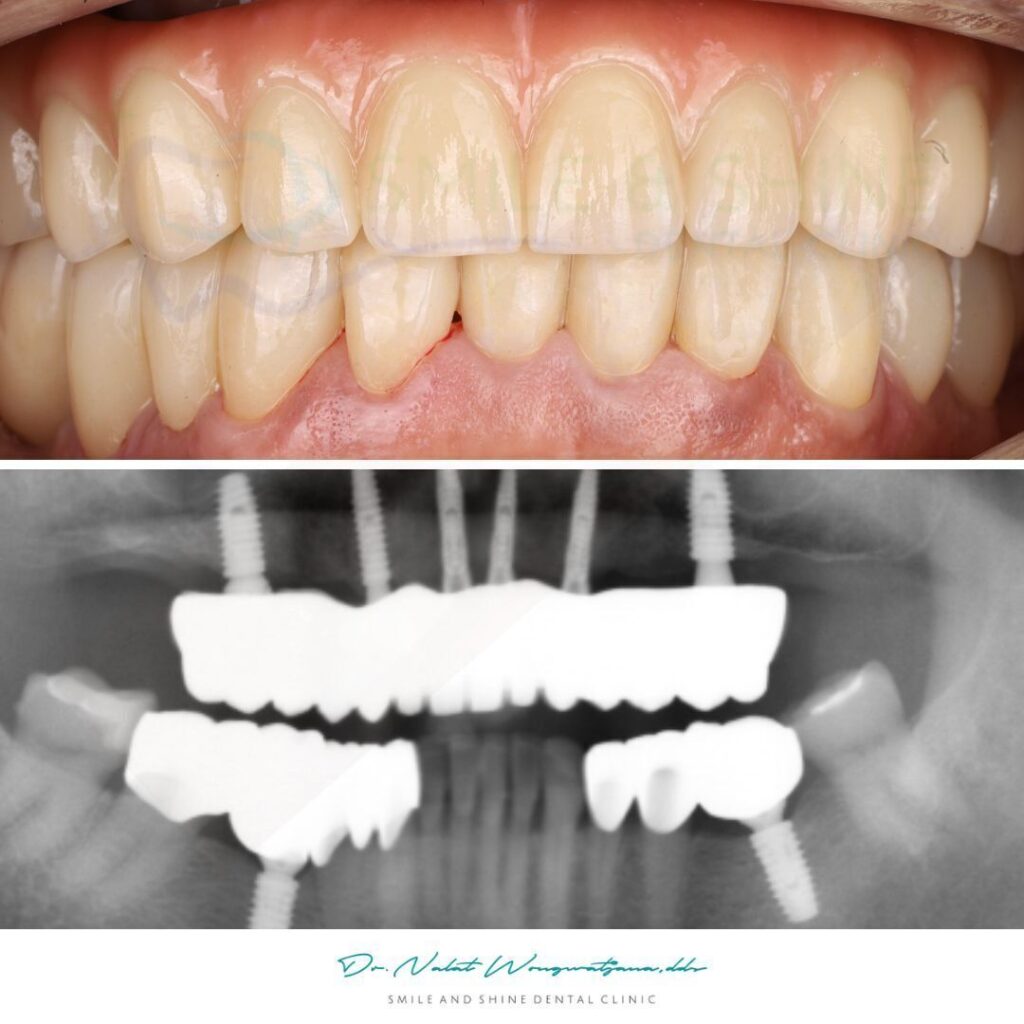

Case Study: ฟันบนแตกต้องถอน ทำ All-on-6 แต่ฟันล่างยังเก็บไว้ได้

ในเคสตัวอย่างนี้

สภาพฟันก่อนการรักษา

- ฟันบนมี รากแตกหลายซี่

- ไม่สามารถซ่อมแซมให้ใช้งานระยะยาวได้

- มีการติดเชื้อและโครงสร้างฟันเสียหาย

ดังนั้นจึงวางแผน

ถอนฟันบนทั้งหมดและทำ All-on-6

แต่ในขณะเดียวกัน

ฟันล่างยังสามารถเก็บไว้ได้

จึงเลือกแนวทางรักษา

- รากฟันเทียมแบบซี่เดี่ยวบางตำแหน่ง

- ครอบฟันเพื่อเสริมความแข็งแรง

- ปรับแนวการสบฟันใหม่ให้สมดุลกับฟันบน

ผลลัพธ์หลังการรักษา

หลังจาก

- ทำ All-on-6 ที่ฟันบน

- บูรณะฟันล่างด้วยรากฟันเทียมและครอบฟัน

คนไข้สามารถ

- เคี้ยวอาหารได้ดีขึ้น

- รอยยิ้มดูเป็นธรรมชาติ

- การสบฟันสมดุล

และที่สำคัญ

ยังคงรักษาฟันธรรมชาติที่ดีไว้ได้